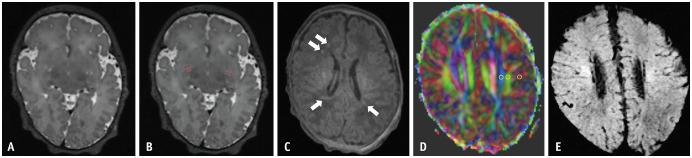

RESULTS

This study included 97 neonates without HII (median gestational age [GA]: 252 days) and 30 with HII (median GA: 252 days). Neonates with HII had smaller BG-PVS volumes (19 mm³ vs. 33 mm³, = 0.001) and fractions (0.29% vs. 0.54%, = 0.003) compared to neonates without HII. The DTI-ALPS index values did not differ significantly between neonates with and without HII ( = 0.54). CGA correlated negatively with BG-PVS measurements (ρ = -0.21 to -0.26, all < 0.05) and positively with DTI-ALPS index values (ρ = 0.22, = 0.014). BG-PVS measurements and DTI-ALPS index values were not significantly correlated (ρ = -0.28 to -0.08, all > 0.05). Multivariable logistic regression revealed a negative association between BG-PVS volume (odds ratio [OR]: 0.96 per mm³ increase, 95% confidence interval [CI]: 0.93-0.99) and fraction (OR: 0.15 per % increase, 95% CI: 0.03-0.79) with HII, while DTI-ALPS index values were not significantly associated with HII (OR: 0.10, 95% CI: 0.00-25.41).

结果

本研究纳入了97例无HII的新生儿(中位胎龄[GA]:252天)和30例有HII的新生儿(中位GA:252天)。与无HII的新生儿相比,有HII的新生儿BG-PVS体积更小(19mm³对33mm³,P = 0.001),分数更低(0.29%对0.54%,P = 0.003)。有和没有HII的新生儿之间DTI-ALPS指数值差异无统计学意义(P = 0.54)。CGA与BG-PVS测量值呈负相关(ρ = -0.21至-0.26,均P < 0.05),与DTI-ALPS指数值呈正相关(ρ = 0.22,P = 0.014)。BG-PVS测量值与DTI-ALPS指数值无显著相关性(ρ = -0.28至-0.08,均P > 0.05)。多变量逻辑回归显示BG-PVS体积(优势比[OR]:每增加1mm³为0.96,95%置信区间[CI]:0.93 - 0.99)和分数(OR:每增加1%为0.15,95%CI:0.03 - 0.79)与HII呈负相关,而DTI-ALPS指数值与HII无显著关联(OR:0.10,95%CI:0.00 - 25.41)。